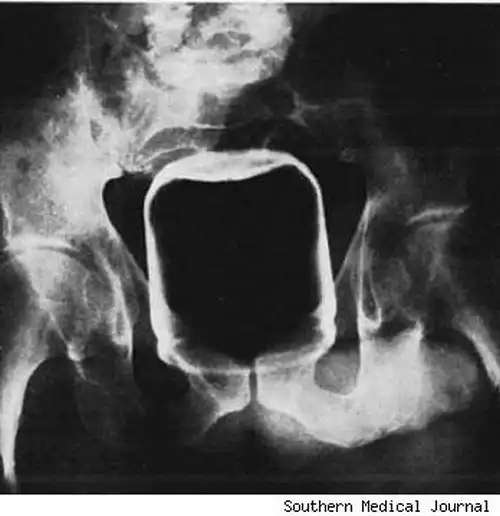

Стеклянная бутылка